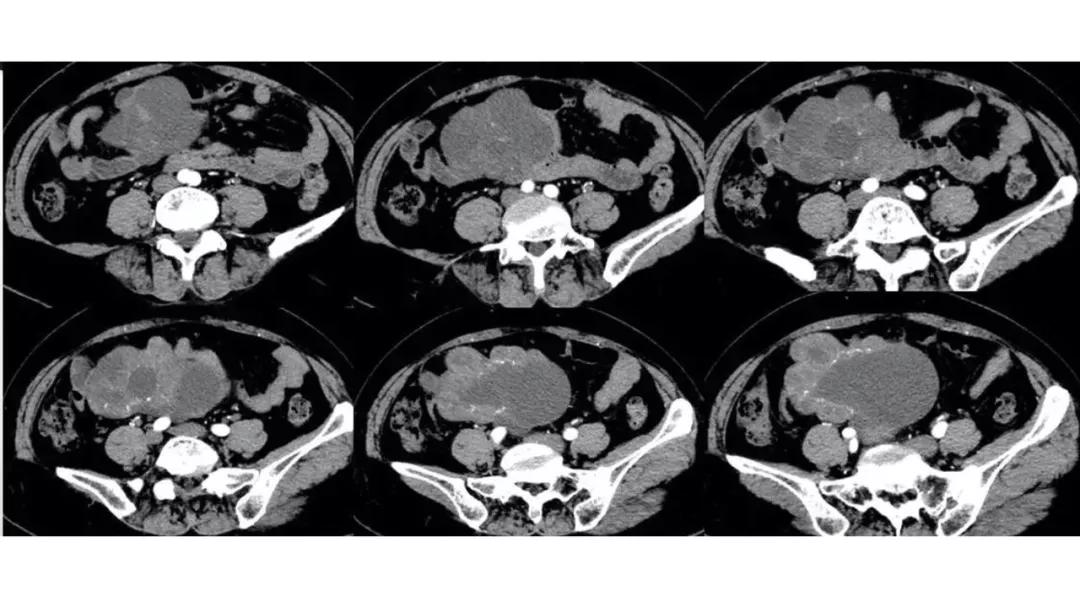

病理:子宫肌瘤粘液样变性

病例4 女,32岁,以“月经量增多伴经期延长半年。”

缘于患者入院前半年无明显诱因出现月经量增多,卫生巾由原来3包余增至5包不等,伴血块,经期由原来7天延长至10-15天不等,无痛经,无月经周期改变,无阴道异常排液,无畏冷、发热,无头晕、乏力等不适,未重视,未诊治。期间症状持续。2月前就诊我院,查彩超示:“子宫体大小约5.7*5.3*4.6cm,内膜厚约0.6cm,回声不均,左卵巢旁探及大小约4.2*3.5cm低回声区。”建议治疗,患者及家属表示考虑。期间症状持续,今就诊我科门诊,要求住院手术治疗,无腹痛等不适,门诊拟“卵巢囊肿”收住入院。既往史:2007年剖宫产一次,术顺。月经史:15 7/25 lmp2018.05.14,量中,无痛经。婚育史:已婚,1-0-3-1,末孕2007年剖宫产娩一男婴,儿子及丈夫体健。个人史、家族史均无特殊。

CA125 335.5(U/mL);2018-05-30 彩超:子宫宫体大小约5.6㎝×6.3㎝×4.9㎝,形态正常,宫壁回声欠均,内膜厚约1.8cm,回声不均。CDFI:子宫内未见明显异常彩色血流信号。左附件区探及一混合回声团块,大小约9.8㎝×7.9㎝,CDFI:其实性部分可见少许彩色血流信号。右附件区未见明显包块回声。

病理:卵巢子宫内膜样癌